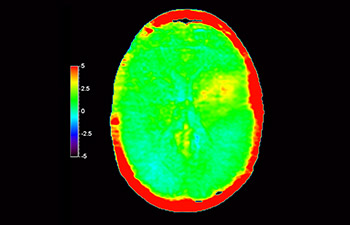

Dans une société où les troubles neurologiques sont importants, Philips s’engage à fournir une qualité de diagnostic irréprochable et la meilleure orientation thérapeutique pour tous les patients. De nos jours, même si l’IRM est une référence en imagerie neuro-oncologique, sa précision en termes de classement des tumeurs et l’évaluation du suivi du traitement peuvent être davantage améliorées. 3D APT (Transfert de proton amide) est une nouvelle méthode d’IRM cérébrale unique et sans contraste qui répond au besoin de fiabilité pour les diagnostics neuro-oncologiques. 3D APT utilise la présence de protéines cellulaires endogènes pour produire un signal RM qui est directement lié à la prolifération cellulaire, indicateur de l’activité tumorale. 3D APT peut aider les professionnels de santé formés à différencier les gliomes cérébraux de haut grade par rapport aux gliomes cérébraux de bas grade, ainsi que l’évolution de la tumeur par rapport aux effets du traitement1.

avec 3D APT